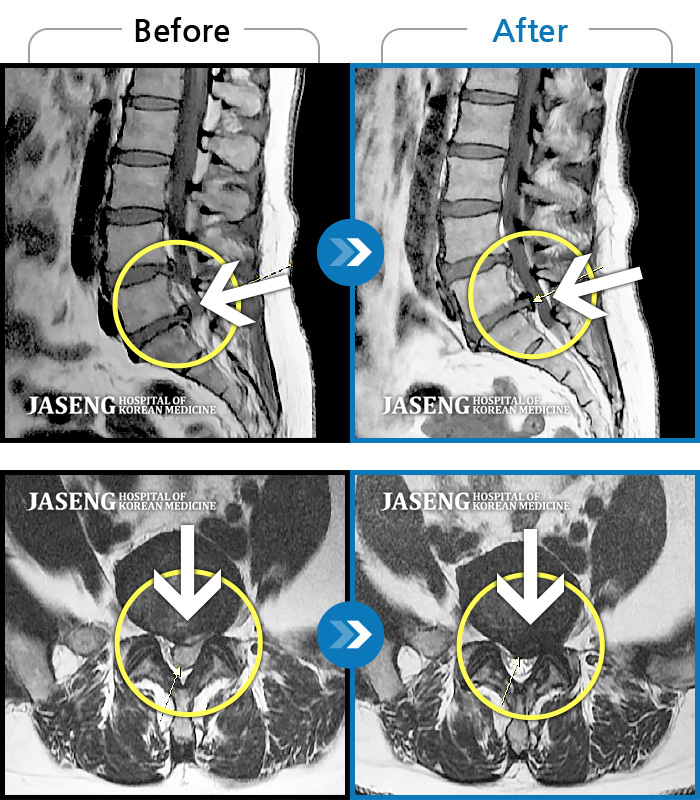

허리디스크

울산 · 정운석 원장

우측 하요추부 통증-우측 둔부-소퇴 후면 통증/비증

촬영시기

2021.08.08 ~ 2021.08.13

2021.08.20